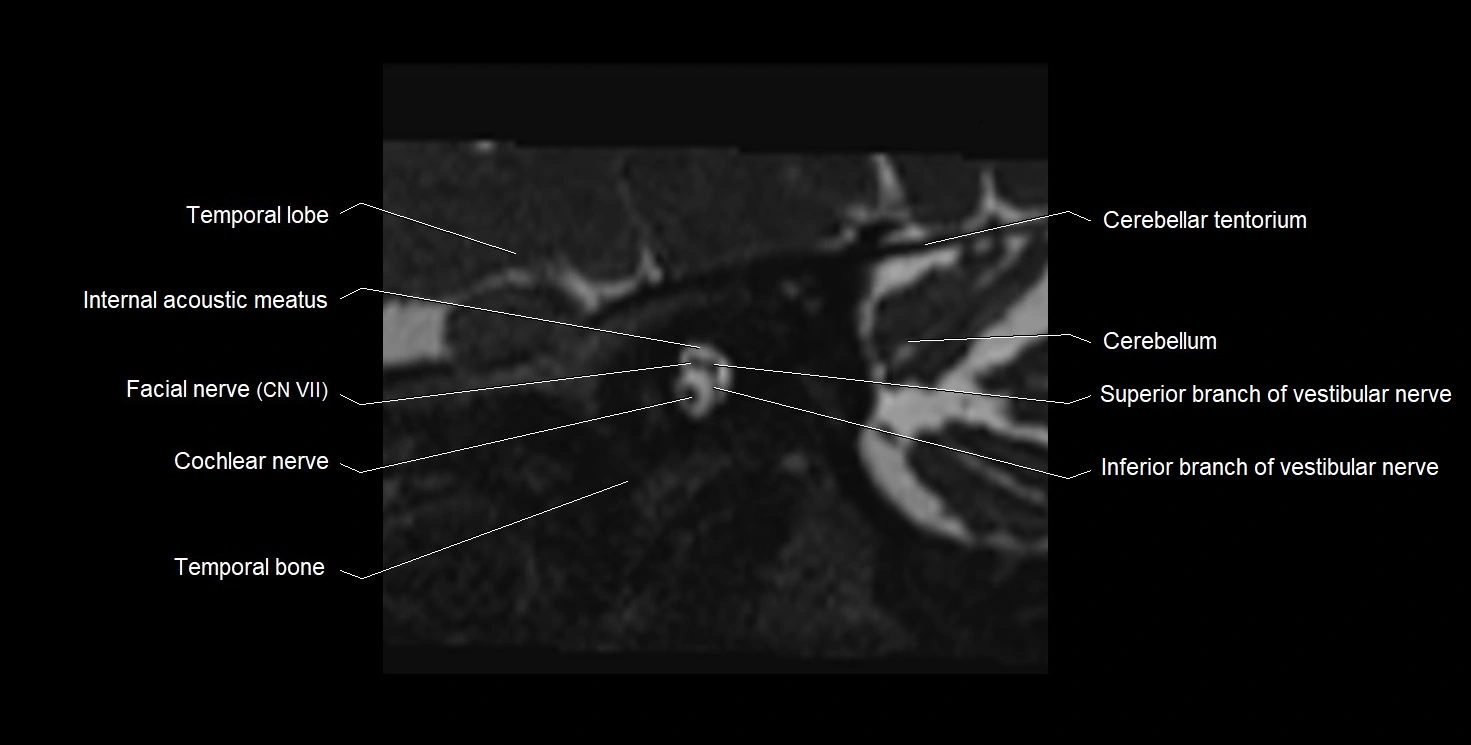

MRI images

image